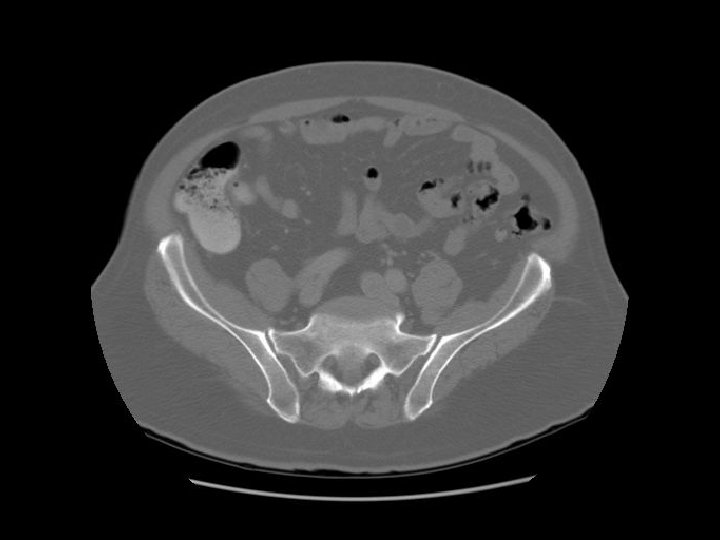

Rt common iliac artery IVC Lt common iliac artery

Arrows are pointing to the common iliac veins joining to form the IVC. Left